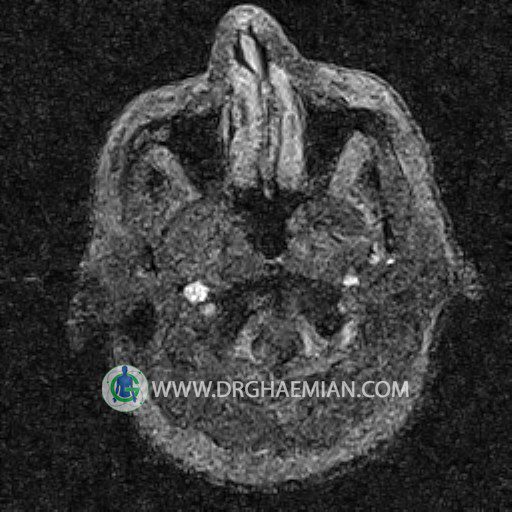

ام آر وی یک روش تصویربرداری دقیق و غیر تهاجمی است که برای معاینه ورید های بدن و ارزیابی سلامت رگ ها استفاده می شود. ورید ها خون را از اعضای بدن به قلب باز می گرداند تا دوباره اکسیژن و مواد مغذی به خون داده شود. ام آر وی جریان خون را ارزیابی و موارد غیرعادی مضر مانند لخته های خونی را شناسایی می کند. در این کیس ترومبوز دیواری مغز در سینوس عرضی راست و ترمبوز جزئی در سینوس عرضی چپ دیده می شود.

– Narrowing of left transverse sinus with filling defect & inthimal irregularity

suggestive for partial thrombosis

– Inthimal irregularity in anterior wall of right transverse sinus suggestive for mural thrombosis

are seen